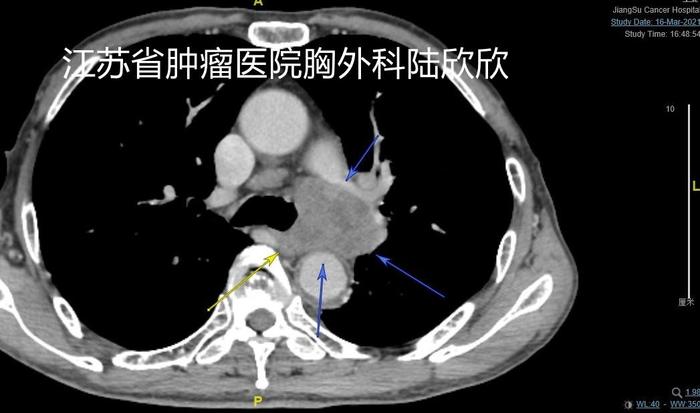

上图可见此患者巨大的转移纵隔淋巴结融合成团,压迫和侵犯肺动脉和食管。3个蓝色箭头指示的是纵隔淋巴结融合成团。黄色箭头指示的是食管受压。